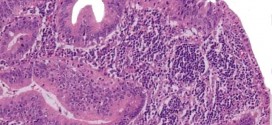

Leer MásCÁNCER DE YEYUNO

El cáncer de yeyuno. El yeyuno se encuentra entre el duodeno y el íleon. El cambio desde el duodeno hasta el yeyuno se define generalmente como ángulo duodenoyeyunal. En humanos adultos, el intestino delgado es por lo general entre 5,5 y 6 m de largo, de los cuales 2,5 m corresponden al yeyuno. El yeyuno es la segunda porción del …